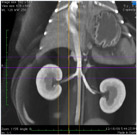

CT dokáže, na rozdíl od RTG, pacienta zobrazit v příčných řezech – výrazně lépe se tedy v CT obraze (ve srovnání s RTG) lékaři orientují a veškeré patologie jsou zřetelnější a snadněji odlišitelné. CT umí dělat i 3D snímky (spojením řezů v počítači). CT vyšetření je indikováno jako doplňující vyšetření, které by mělo pomoci při nejasném nálezu na ultrazvukovém vyšetření nebo klasickém RTG snímku.

V akutních (neodkladných) indikacích používáme CT především pro zobrazování hlavy – mozku při cévních mozkových příhodách a úrazech hlavy, neboť velmi dobře zobrazí nitrolební krvácení. Spolehlivě zobrazí i úrazové změny orgánů hrudníku, břicha, pánve i zlomeniny kostí.

CT angiografie (vyšetření cév pomocí CT) se používá především pro zobrazení velkých tepen a také pro zobrazení mozkových tepen, je metodou volby při diagnostice portosystémových shuntů. Může zcela nahradit klasické angiografické vyšetření.